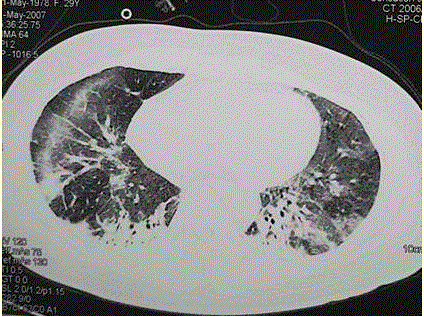

问题 患者女,29岁。间断干咳10年余,加重4个月,伴进行性呼吸困难1个月。病程中出现双手及双足非凹陷性肿胀、双侧膝关节及双侧肘关节对称性肿痛,面部出现细小红色丘疹。体检:T 36.5℃,P 88次/min,R 22次/min,BP 110/75 mmHg,SpO 93%(自然)。额部、前胸及后背散在红色小丘疹,双肺呼吸音增强,双肺中下肺野可闻及爆裂音,右肺明显。胸部CT 如图所示。 应采取的治疗措施包括

选项 A.吸氧 B.无创通气 C.糖皮质激素治疗 D.及早插管上机,给予机械通气 E.大剂量抗生素治疗 F.糖皮质激素+免疫抑制剂 G.雾化吸入糖皮质激素及支气管扩张剂

答案 ACF